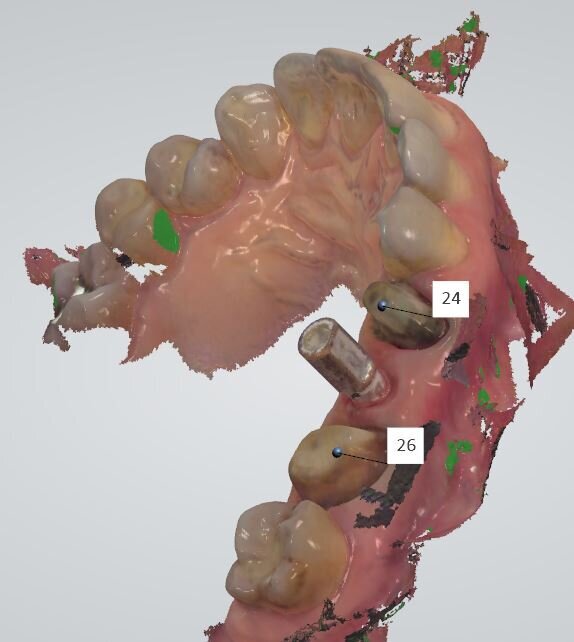

La terapia endodontica estesa agli elementi adiacenti ha consentito di eseguire un provvisorio che ha permesso alla paziente di non subire il disagio estetico e funzionale del mancato carico dell’impianto. Dopo due mesi si è provveduto a rilevare le impronte per la riabilitazione finale. Abbiamo utilizzato un sistema digitale (Trios-Trishape) che seguendo la procedura di lettura rileva le varie impronte dal provvisorio, al tragitto transmucoso, in tal caso è necessario provvedere a posizionare i fili retrattori che siamo soliti utilizzare nella lettura del finish line e solo al momento della lettura andiamo a rimuovere il 2° filo e a svitare la vite di guarigione o il moncone provvisorio così da non determinare il collasso dei tessuti del tragitto transmucoso implantare (Fig. 6). Dopo l’impronta dei tessuti e dei monconi degli elementi naturali si procede a segnalare gli elementi da protesizzare (Fig. 7) e successivamente si posiziona il transfer dell’impianto che nel sistema digitale è rappresentato dallo scan body o corpo di scansione (Fig. 8).

Fig. 7 - La schermata dell’impronta rilevata con sistema IOS Trishape.

Fig. 8 - Posizionamento dello scan body dell’impianto Conelog utilizzato dal diametro di 4.3.

Fig. 9 - Stessa schermata con lo scan body e con la numerazione degli elementi selezionati per la realizzazione protesica definitiva.